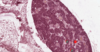

parathyroid

adipocyte

parathyroid

Oxyphil cell.